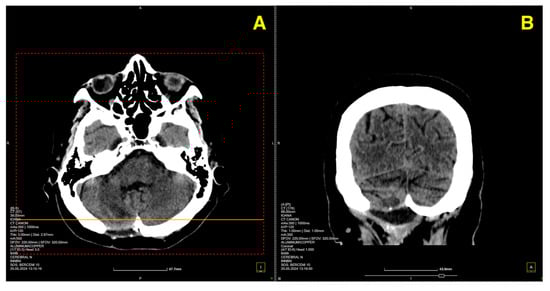

Given the patient’s symptoms and neurological findings, an MRI scan of the brain was performed to further evaluate potential cerebellar or vestibular pathology. The MRI revealed a well-circumscribed cavernous malformation (cavernoma) located in the right cerebellar hemisphere (Figure 1 and Figure 2). The lesion appeared hyperintense on T2-weighted imaging, with a peripheral rim of hemosiderin, suggestive of prior microhemorrhages. The lesion measured approximately 1.5 cm in diameter and was localized to the posterior fossa, without any evidence of acute hemorrhage or mass effect. The surrounding cerebellar structures, including the brainstem, showed no significant compression or deviation. Magnetic resonance angiography (MRA), performed to rule out vascular anomalies, confirmed the absence of arteriovenous malformations or other vascular abnormalities (Figure 1D and Figure 2D). The lesion was determined to be isolated, with no direct involvement of the major cerebellar arteries or veins.

Figure 2. The red arrow highlights the cerebellar cavernous malformation (CCM) located in the right cerebellar hemisphere. This lesion is characterized by its hypointense signal on T1-weighted MRI images (AC), consistent with prior microhemorrhages and hemosiderin deposition surrounding the malformation. The lesion’s distinct margins and location, without significant mass effect on adjacent structures such as the brainstem and fourth ventricle, are emphasized by the arrow. The MRA (D) further confirms the absence of vascular anomalies, distinguishing the lesion as a solitary cavernoma without associated arteriovenous malformation.